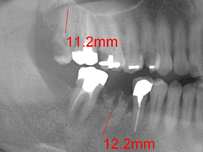

親知らずの抜歯・顎関節症の治療などが主な例としてあげられます。

口腔外科の専門性を活かして、より安全でスピーディーな抜歯と適切な術後のフォローをさせていただきます。痛みが出た際にはすぐに当院までご相談ください。